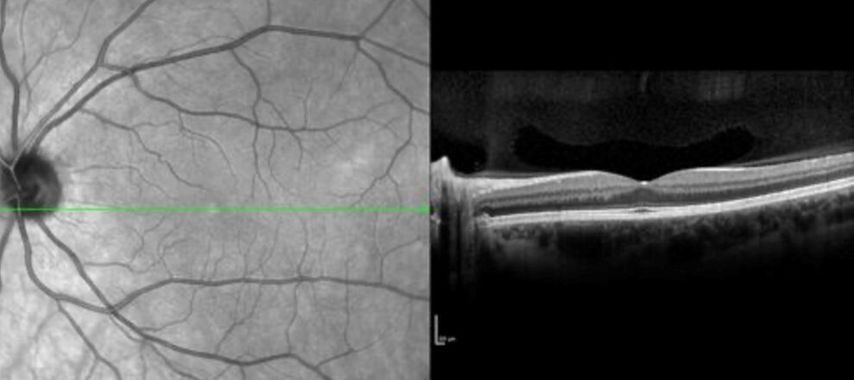

Abb. 1: Retinale OCT-Aufnahme einer MS-Patientin mit diskreter retinaler Atrophie (Bild: Gabriel Bsteh)

Die Messung von retinaler Schichtatrophie mittels der optischen Kohärenztomographie (OCT) ermöglicht eine zuverlässige Bestimmung neuroaxonaler Schädigung für das Monitoring des Krankheitsverlaufs bei Multipler Sklerose (MS). Eine neue Studie gibt Einblick in die Rolle der Genetik: Träger:innen des rs10191329-Risikogenotyps im DYSF–ZNF638-Locus zeigen in einer prospektiven RMS-Kohorte eine signifikant beschleunigte Atrophie retinaler Schichten in der OCT. Pro Risikoallel nahm die jährliche Atrophierate der peripapillären retinalen Nervenfaserschicht (pRNFL) um 0,10% pro Jahr und der Ganglienzell- und inneren Plexiformschicht (GCIPL) um 0,11% pro Jahr zu – unabhängig von Alter, Krankheitsaktivität, Therapie und Ancestry-Komponenten. Die Befunde stützen die Hypothese einer genetisch vermittelten neuroaxonalen Vulnerabilität jenseits primär immunologischer Mechanismen.